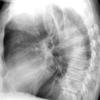

Ao Diss 3

Date: 02/26/2006

Views: 2885